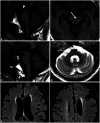

Parkinsonism is a clinical syndrome presenting with bradykinesia, tremor, rigidity, and postural instability. Nonmotor symptoms have recently been included in the parkinsonian syndrome, which was traditionally associated with motor symptoms only. Various pathologically distinct and unrelated diseases have the same clinical manifestations as parkinsonism or parkinsonian syndrome. The etiologies of parkinsonism are classified as neurodegenerative diseases related to the accumulation of toxic protein molecules or diseases that are not neurodegenerative. The former class includes Parkinson's disease (PD), multiple-system atrophy, progressive supranuclear palsy, and corticobasal degeneration. Over the past decade, clinical diagnostic criteria have been validated and updated to improve the accuracy of diagnosing these diseases. The latter class of disorders unrelated to neurodegenerative diseases are classified as secondary parkinsonism, and include drug-induced parkinsonism (DIP), vascular parkinsonism, and idiopathic normal-pressure hydrocephalus (iNPH). DIP and iNPH are regarded as reversible and treatable forms of parkinsonism. However, studies have suggested that the absence of protein accumulation in the nervous system as well as managing the underlying causes do not guarantee recovery. Here we review the differential diagnosis of PD and parkinsonism, mainly focusing on the clinical aspects. In addition, we describe recent updates to the clinical criteria of various disorders sharing clinical symptoms with parkinsonism.